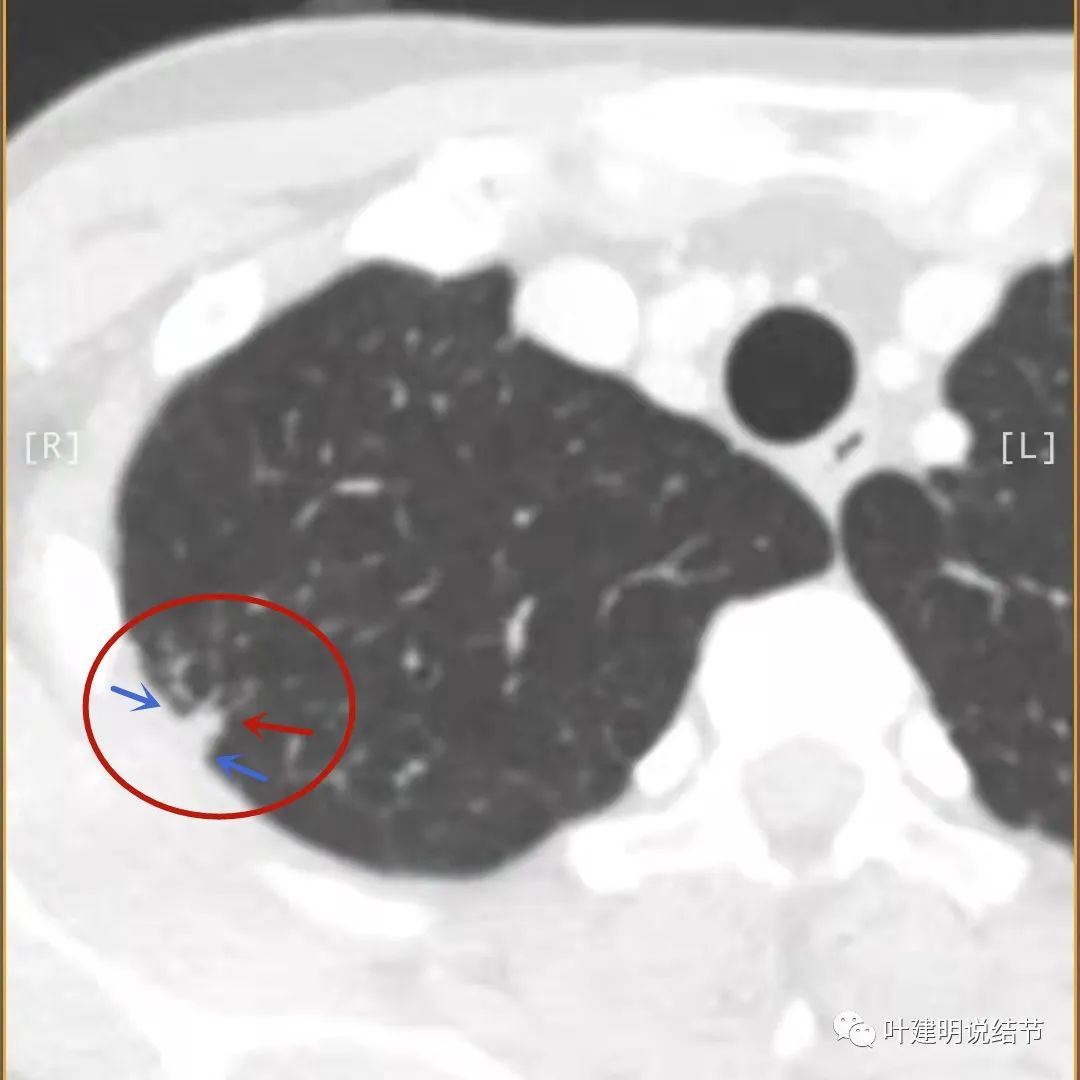

主病灶此层面似三角形,邻近胸膜增厚(蓝色箭头),结节实性部分密度较高(粉色箭头),边缘显模糊(砖色箭头)

上图与恶性较为符合,空洞性病灶,壁厚薄不均,增厚部分还凹凸不平(细红色箭头所指)

上图磨玻璃部分密度过低,且与正常肺组织界限模糊(砖色箭头),粉色箭头示囊壁密度过高的点状,蓝色箭头示邻近胸膜处的增厚

上图也像恶性,但整个囊壁的密度感觉过高了点,边缘磨玻璃淡、散且模糊,邻近胸膜有增厚